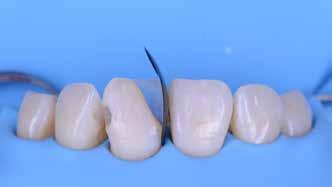

A cikkünkben bemutatásra kerülő eset ellátása során preparációt héjak készre vitele során a platinafólia technikát alkalmaztuk.

preparációt nem igénylő héjak készítése mellett döntöttünk. A alkalmaztuk. Annak ellenére, hogy az elkészítésre kerülő héjak rendjelentős törésveszéllyel állunk szemben, összességében mégis

javasoljuk e módszer alkalmazását.

A fogászati kezelések során manapság már nem kizárólag az esztétikai megjelenés helyreállítására törekszünk. Sokszor a kedvezőtlen esztétikai megjelenés hátterében álló okok következményes módon a fogazat funkcionális működését is károsítják, így a kezelések során ezeknek a helyreállításával is foglalkoznunk kell. A különböző funkcionális és esztétikai diszkrepanciák kezelésére számtalan módszer létezik, ám ezen fogászati beavatkozások mindegyikében közös, hogy a kivitelezésük során nagyon szoros együttműködésre van szükség a kezelést végző fogorvos és a munkáját segítő fogtechnikus között. Az alábbi esetbemutatás során egy fiatal hölgypáciens fogazatának héjak alkalmazásával történő esztétikai és funkcionális rehabilitációját szeretnénk ismertetni.

A kezelés megtervezése során kifejezett jelentősége van annak, hogy jó kommunikáció legyen a páciens, a fogorvos és a fogtechnikus között. A páciens leendő fogazatának természetes megjelenését a kezelésben részt vevő team szakmai felkészültsége, gyakorlati tapasztalata és a kezelés sikerességének irányába történő elkötelezettsége biztosítja. A beavatkozások megkezdése előtt megtörtént a páciens anamnézisének a felvétele, valamint a klinikai kivizsgálását is elvégeztük. Ezt követően lenyomatokat készítettünk a kiindulási állapotról, majd a kiindulási helyzetet extra- és intraorális fotók segítségével is rögzítettük (13. a-c. ábra).

A kezeléstervezés egyik legfontosabb lépése a mock-up elkészítése. A mock-up alapjául szolgáló wax-up-ot (felviaszolás) is ugyanolyan részletességgel kell a fogtechnikusnak elkészíteni, mintha azok már a végleges fogpótlások alapjául szolgáló mintázatok lennének. A mock-upnak nagyon pontosan kell illeszkednie, valamint a tervezett fogpótlás meg-

jelenését is rendkívül élethűen kell reprezentálnia. Ahhoz, hogy a páciens mock-uppal kapcsolatos első benyomásai kedvezőek legyenek, a mock-up színének a páciens „szemfehérjének” színével meg kell egyeznie. A kezelési cél páciens által történő elfogadása és a tervezett eredménnyel kapcsolatos „wow-effektus” kialakulása nagyban függ a páciensben az első megtekintés során kialakult első benyomásoktól.

Az eddigi tapasztalataink szerint a páciensek jelentős többsége egyértelműen kifejezi az elégedettségét, ha a mock-up megfelel az eredeti elképzeléseiknek. A bemutatásra kerülő esetben is ez történt. A tervezett végeredmény megtekintését követően a páciens azonnal kérte az általunk javasolt kezelési tervben ismertetett beavatkozások elvégzését. A héjak alapanyagául az Ivoclar Vivadent által gyártott A1-es színű Telio CS kerámiát javasoltuk. Az anyagválasztás hátterében az állt, hogy ez az anyag nagy keménységgel rendelkezik, valamint az, hogy a felszínét nagy simaságúra lehet polírozni. A páciens rendkívül fiatal életkora is azt a terápiás koncepciót erősítette, hogy a kezelés során lehetőség szerint kizárólag non-invazív beavatkozásokat alkalmazzunk.

A platinafólia technikát 1896 óta alkalmazzák. Napjainkra az eredeti eljárás már kismértékben módosításra került, de lényegében ugyanazzal a módszerrel történik a platinafóliára készülő koronák és héjak elkészítése. A minimál invazív fogászat egyre szélesebb körben történő elterjedésének köszönhetően ez az eljárás a reneszánszát éli. A pácienseink egyre gyakrabban szeretnék a fogaik alaki, színi vagy helyzeti rendellenességeit a lehető legkisebb saját foganyagveszteség árán korrigáltatni. Az eljárás során 0,025 mm vastag 99,9%-os tisztaságú platinafólia kerül alkalmazásra. Amennyiben a megfelelő technikai háttér és a beavatkozások elvégzéséhez szükséges elméleti és gyakorlati szaktudás is rendelkezésünkre áll, akkor semmi sem állhat az utunkba a pácienseink új mosolyának kialakítása során.

A módszer első lépéseként a gipszből kiöntött csonkokat platinafóliával borítjuk (5. ábra). Az adaptálását követően a felhelyezett fóliát óvatosan eltávolítjuk, felhevítjük, majd ismét visszahelyezzük a csonkokra. Ezt követően történik meg az első kerámiaréteg felvitele (Waschbrand). Az első égetés során csupán egy nagyon vékony réteg kerámia kerül a fólia felszínére (6. ábra). Amikor az égetést követően ezt

a kezdetleges kerámiavázat visszahelyezzük a csonkokra, a kerámia anyagában vékony repedések alakulnak ki. A végleges restaurátum elkészítéséhez szükséges kerámia „köpeny” ekkor áll készen a további kerámiarétegek felvitelére és kiégetésére (opaker réteg, dentin- és zománcmassza felvitele) (7-10. ábra). A készülő fogpótlás végső formai megjelenése rétegenként kerül kialakításra.

A második égetés során szintén csupán egy nagyon vékony réteg transzlucens opalmassza kerül felhelyezésre. A restaurátum formai megjelenésének és a felszíni textúrák kialakítására csak ezt követően kerül sor. A fényégetés során nem alkalmazunk glazúrmasszát. A készre vitel során elérni kívánt, magas fényű polírt kézi eszközök alkalmazásával alakítjuk ki. A restaurátumok végső kidolgozását követően a platinafóliát egy csipesz segítségével óvatosan eltávolítjuk, majd a kifejezetten vékony héjakat a kontroll mintára helyezzük. Ezt követően a pótlások megfelelő illeszkedésén kívül a funkcionális elmozdulások közben kialakuló érintkezéseket és a kontaktpontokat is ellenőrizzük. Az ilyenkor esetlegesen szükségessé váló korrekciók elvégzésére a Ducera® LFC (Dentsply Sirona) kerámiaanyagot használjuk. A kész munka fogorvosi rendelőbe való szállítása előtt kifejezett jelentőséggel bír az elkészült restaurátumok gondos becsomagolása. Az átadni kívánt fogpótlások sérülésmentes szállíthatóságának biztosítása elengedhetetlen az eddigi munkánk védelme szempontjából.

A héjak átadását követően kialakuló állapot valósághű módon történő bemutatása érdekében próbapasztát alkalmaztunk (Try-In-Paste; Variolink® Esthetik Try-In-Paste, Ivoclar Vivadent) (11. ábra). A próba során ellenőrizzük a héjak színét, formáját és transzparenciáját. A próbapaszta alkalmazásának egyik lényeges pontja, hogy a paszta színe egyezzen meg a végleges beragasztás során alkalmazni kíván ragasztóanyag színével. A héjak végleges rögzítése során mindig adhezív rendszereket használunk.

A preparálást nem igénylő héjak általában nagyon vékonyak, és sajnálatos módon ebből adódóan a végleges átadásuk előtt történő előkészítés során könnyen eltörhetnek. Csupán a páciensek saját fogain történő végleges rögzítés révén kapják meg azt az alátámasztottságot, amely a végleges töréssel szembeni ellenálló képességüket biztosítja. A fogpróba során a héjakat egyesével a fogakra helyezzük, és ellenőrizzük a pontos illeszkedésüket, valamint az approximális kontaktpontok megfelelőségét. Amenynyiben mindent rendben találtunk, úgy hozzákezdhetünk a héjak adhezív módszerrel történő rögzítéséhez szükséges előkészületek elvégzéséhez. Első lépésként a héjak elhorgonyzásul szolgáló fogak abszolút izolálását követően, meggyőződünk a ragasztási felület leszáríthatóságáról. Ezt követően az adhezív rögzítés során felhasznált fogfelszínt – az alkalmazni kívánt adhezív rendszer

nak megfelelően – előkészítjük (orthofoszforsavval történő savazás, lemosás, szárítás és bond réteggel történő fedés). Ezzel egyidejűleg a ragasztásra kerülő héjak is előkészítésre kerülnek (hidrofolysavval történő savazás, lemosás, szárítás, szilanizálás, bond réteggel történő fedés, és végül az alkalmazni kívánt ragasztóanyag felvitele). Ezután a héjakat a fogak felszínén egyesével pozicionáljuk, majd néhány másodpercen keresztül polimerizációs lámpa segítségével megvilágítjuk. Ezt követően a kifolyó ragasztófelesleget eltávolítjuk, majd elvégezzük a restaurátumok végső polimerizálását. A héjak végleges rögzítését követően az esetlegesen visszamaradt ragasztómaradványok eltávolításra kerülnek, valamint ellenőrizzük az okklúzió és artikuláció közben létrejövő fogérintkezéseket. Az optimális esztétikai eredmény biztosítása érdekében kiemelt jelentősége van a papillák helyreállításának (rózsaszín esztétika). A modern fogorvoslás egyik kiemelt célja a fehér- és rózsaszín esztétika közti harmonikus egyensúly megteremtése. A papillák színe, nagysága és szimmetrikus megjelenése meghatározó szerepet tölt be a rózsaszín esztétika kialakításában. Az íny lefutása ugyancsak rendkívül jelentős mértékben befolyásolja a páciens fogazatának esztétikus megjelenését.

A cikkünkben bemutatásra kerülő eset ellátása során preparációt nem igénylő héjak készítése mellett döntöttünk. A héjak készre vitele során a platinafólia technikát alkalmaztuk. Annak ellenére, hogy az elkészítésre kerülő héjak rendkívül vékonyak, és ezáltal a végleges rögzítésük előtt jelentős törésveszéllyel állunk szemben, összességében mégis olyan minimál invazív kezelési eljárásnak számítanak, amely segítségével kifogástalan esztétikai eredményeket lehet elérni. A fent leírtak alapján bátran javasoljuk e módszer alkalmazását.